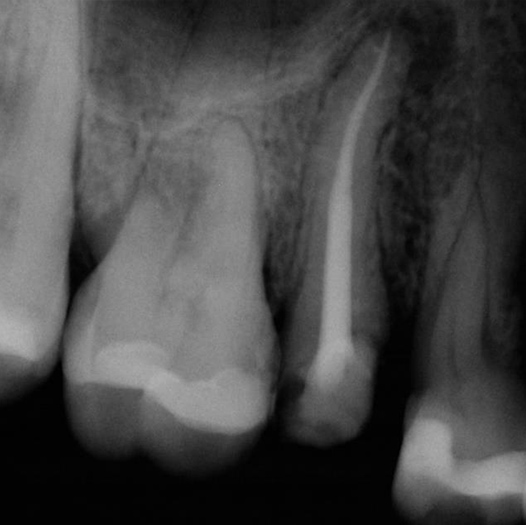

Before

After

Before Root Canal treatment

After Root Canal treatment